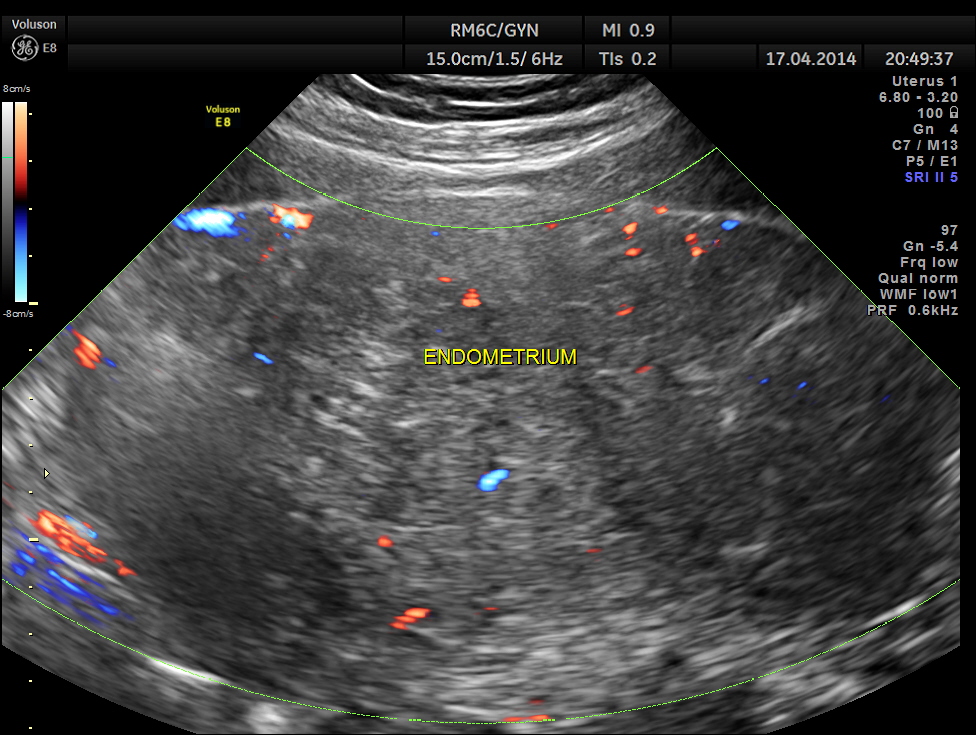

Uterus was massively enlarged and showed a large fibroid . Uterine texture also showed features of adenomyosis and endometrial thickening.

The ultrasound gave us a few inconclusive findings . Uterus was massively enlarged ; a large fibroid was seen ; adenomyosis was seen ; endometrium was thickened ; two large mass lesions were seen in the right upper quadrant and right lumbar region . But it was difficult to ascertain the origin of these extra uterine masses .